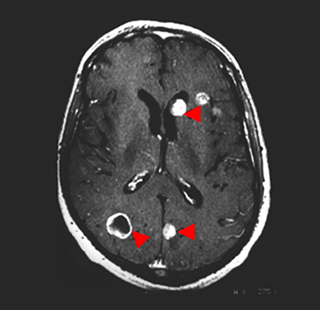

뇌 MRI

- 폐암은 뇌로 전이될 가능성이 높기 때문에, 뇌 MRI는 폐암 환자에서 뇌 전이를 확인하는 데 사용됩니다. 조기에 뇌 전이를 발견하면 치료 계획을 수정하여 환자의 예후를 개선할 수 있습니다.